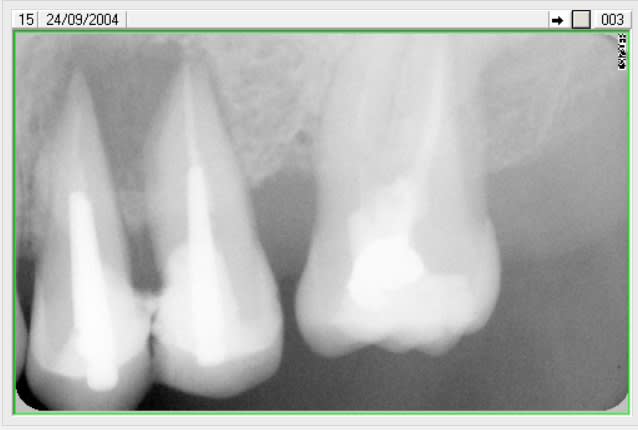

regarde ce cas ,il y a bien un kyste entre les 2 pm ?

sans rien toucher aux endos ,le fait d'enlever une dent , de cureter et remettre ça à suffit .

quoi en penser ? que l'endo (rte ) n'est pas indispensable en tout cas !!!!!!

2004 ol0ef3 - Eugenol

2006 osdd8r - Eugenol

2015 ahvvuu - Eugenol